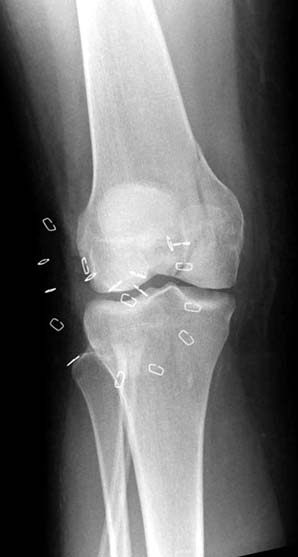

[Ortho] Нелеченный перелом Hoffa

Здесь представлены различные варианты фиксации перелома, а также снимки

комбинации перелома с повреждением хряща (12-19). Пластика хряща

OsseoFit и установка custom made plate.